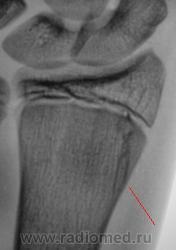

Пациент - подросток пришел с папой в рентгеновский кабинет, с просьбой коллеги хирурга "сделать рентгенографию лучезапястного сустава". Из анамнеза известно, что накануне, ребенку в область лучезапястного сустава ударился мяч - играли в футбол. Произвели рентгенографию.

А Вас ничего не смущает в области метафиза?

А это не похоже на "трещину"? или что "это" может быть?

На мой взгляд, больше похоже на перелом. Однако под вопросом. Всё решает клиника и  четкий анамнез - если удар мячом пришелся просто в область сустава, то, скорее всего, это - не травматические изменения. А если удар пришелся в кисть по оси предплечья или перпендикулярно оси - то это перелом.

Здравствуйте Вега! Клини ка есть - боль, есть и отёк.

А такая "фрагментация" эпифиза может быть "нормой". А что скажите по поводу нечеткости и "разорванности" контура эпифиза - красные стрелки. Как будем оценивать "выступ" на фоне зоны росткового хряща - сиреневая стрелка.

Тогда получается эпифизиолиз с дальнейшим переходом на метафиз, а значит ни просто эпифизиолиз а остеоэпифизиолиз, но ведь ростковая зона интактна!